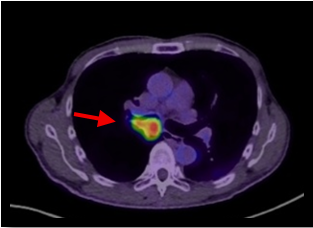

肺がん原発巣の症例。(病変部は赤矢印)

CT画像→病変部がわかりにくい

PET画像 → 解剖部位がわかりにくい

PET画像とCT画像を重ね合わせることで、病変が存在する解剖部位が分かるため診断能が高くなる